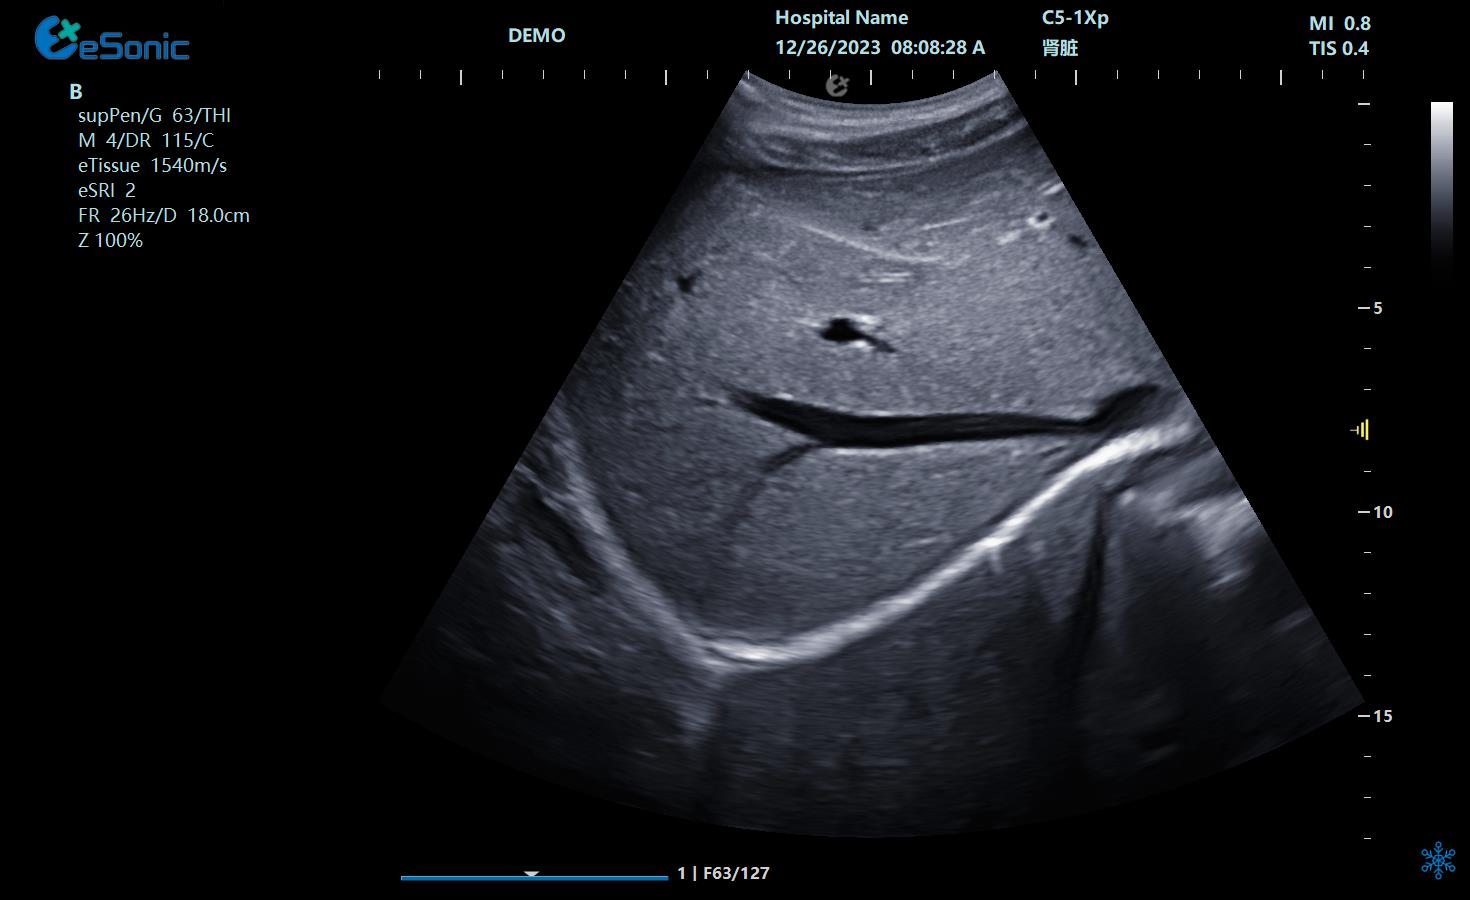

无磁导航